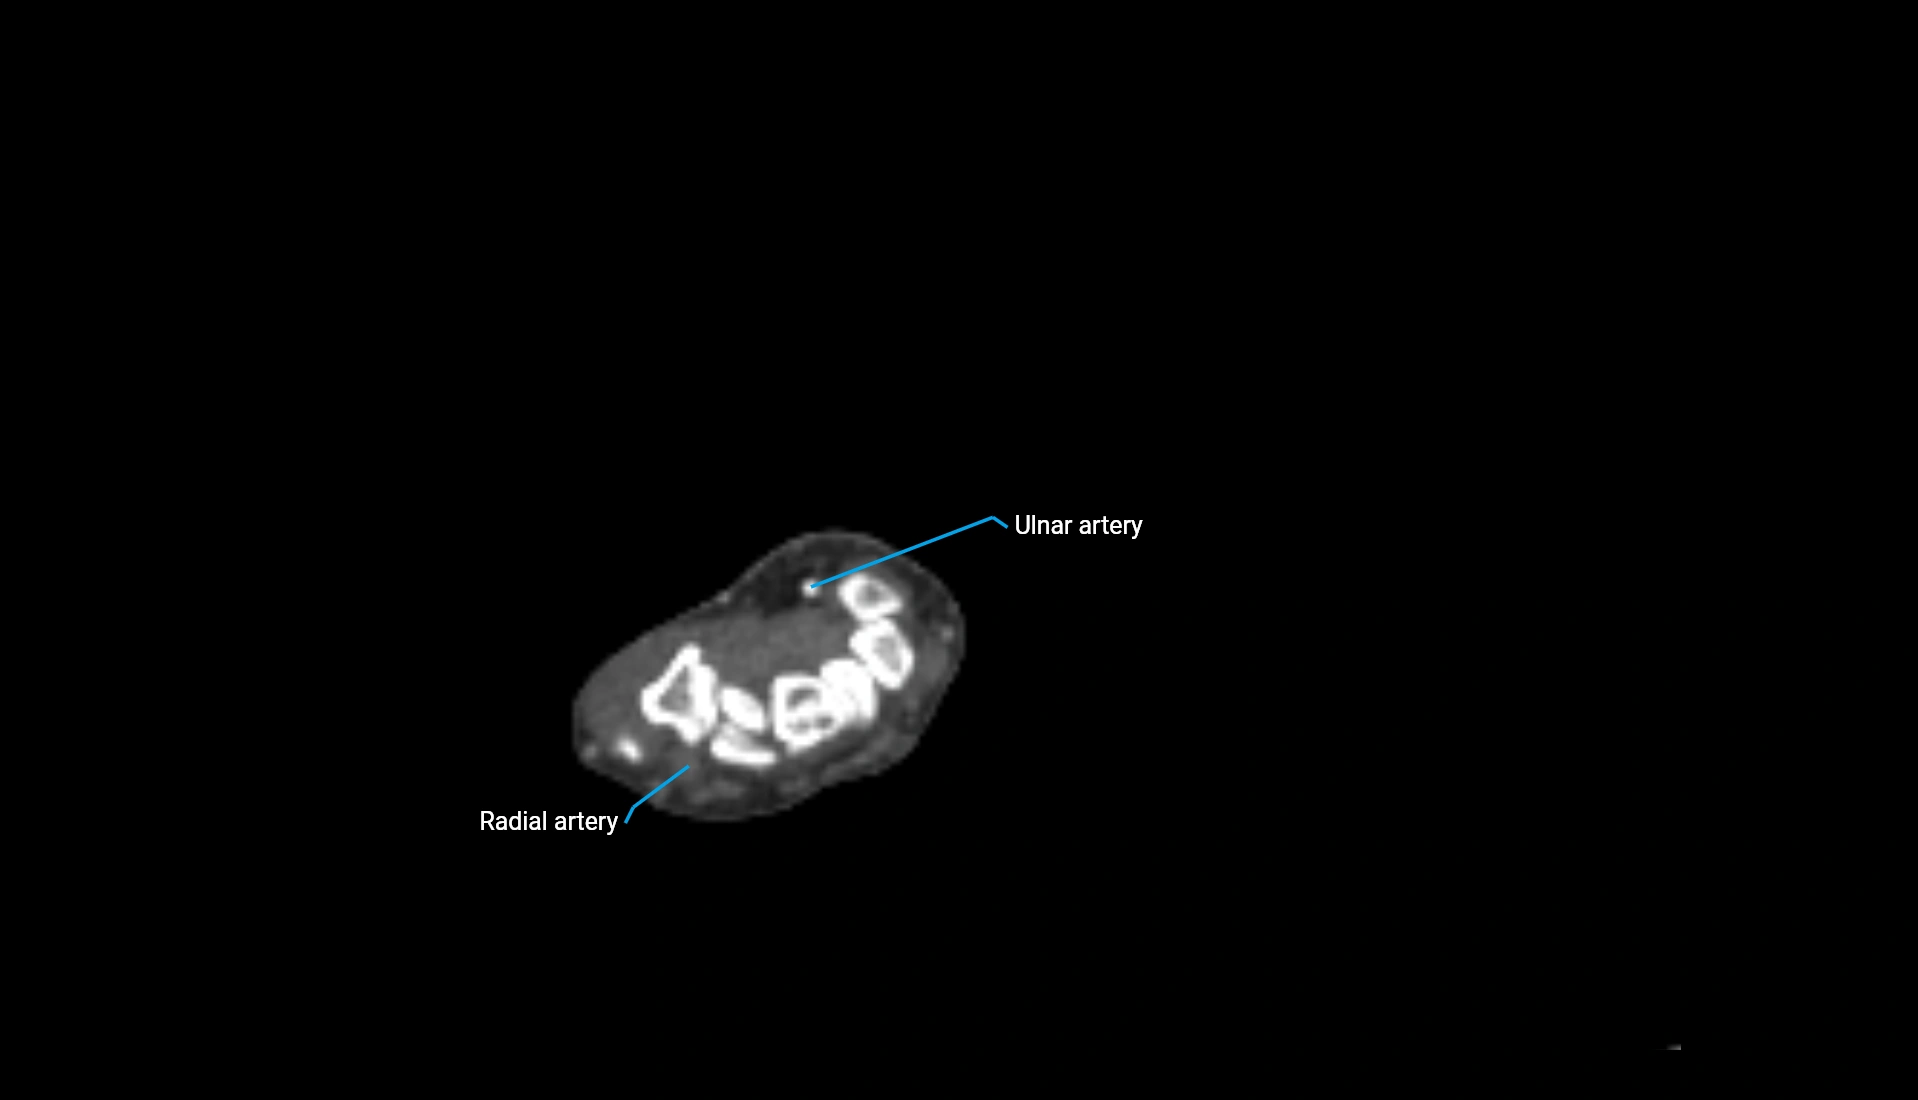

CT Appearance

Non-Contrast CT:

• Cortex: High-density, sharply defined

• Subchondral bone: Dense cancellous matrix

• Articular surface: Smooth concave contour articulating with the capitellum

• Excellent for evaluating bone integrity, alignment, and subtle fractures

Post-Contrast CT:

• Bone: No enhancement

• Joint capsule and synovium: Mild enhancement outlining the joint

• Improves contrast between soft tissues and bony margins

• Useful in detecting subtle joint abnormalities or postoperative changes